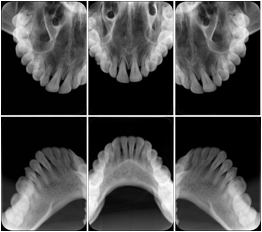

3. A patient in rural Minnesota experiences sudden vision loss and goes to a general ophthalmologist, who acquires OCT images and forwards them electronically along with a Structured Display to a retina specialist six travel hours away. The retina specialist is able to view the images in the standard layout that he is comfortable with, and to confirm that the patient has a choroidal neovascular membrane. He determines that is would be worthwhile for the patient to travel for treatment.

OCT Retinal Study with Cross Section and Navigation Structured Display